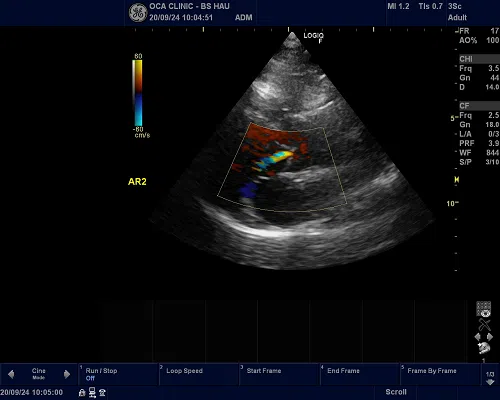

Siêu âm Doppler

Siêu âm Doppler dùng để kiểm tra lưu lượng máu, đo áp lực động mạch phổi . Bác sĩ có thể sử dụng siêu âm doppler màu để lập bản đồ hướng và tốc độ của các dòng máu trong tim.

Thông thường máu chảy về phía đầu dò xuất hiện màu đỏ, máu chảy ra có màu xanh.

Kết quả của siêu âm Doppler có thể kiểm tra, phát hiện một số bệnh tim, mạch máu và đánh giá cung lượng tim.

Hình ảnh sieu âm tim phát hiện bệnh lý hở van 2 lá

Siêu âm tim là giải pháp hiệu quả giúp bác sĩ chẩn đoán cũng như dễ dàng phát hiện ra các bệnh lý liên quan đến tim mạch như hở van tim, suy tim, nhồi máu cơ tim, viêm cơ tim,... Việc này giúp người bệnh có thời gian chuẩn bị tâm lý và nhanh chóng điều trị kịp thời giúp đảm bảo chất lượng sức khỏe trước khi xảy ra các tình trạng xấu hơn.